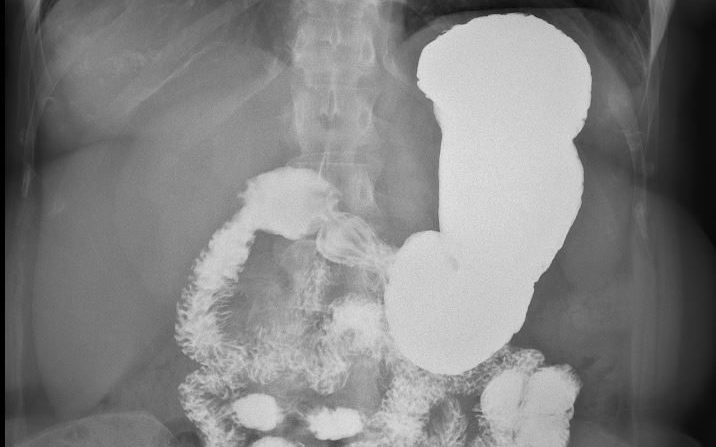

שיקוף חוקן

בדיקה המיועדת להדגמת המעי הגס, לרוב בעזרת חומר ניגוד המוזרק דרך פי הטבעת ולעיתים גם בעזרת ניפוח אוויר לתוך המעי הגס. אורך הבדיקה לרוב עד 30 דקות. תדרשו בהכנה מיוחדת של ריקון המעיים מצואה ב-48 שעות שטרם הבדיקה. הרופא המפנה שלכם יתן לכם הסבר ורשימת חומרי ריקון אותם תצטרכו לקחת.

מה קורה במהלך הבדיקה?

במהלך הבדיקה תתבקשו לשכב על שולחן הבדיקה. קרינת הרנטגן מיוצרת על שפופרת רנטגן יעודית מתחת לשולחן ונקלטת ע"H גלאי התלוי מעליכם בשולחן. אם תדרש לקיחת חומר ניגודי במהלך הבדיקה, הרנטגנאי יספק לכם אותו ויסביר על אופן הלקיחה.